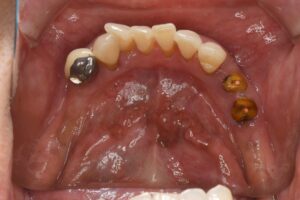

スマートデンチャー(ノンクラスプデンチャー)での入れ歯治療(60代女性)

治療前

バネなしの入れ歯の作成を行なった。